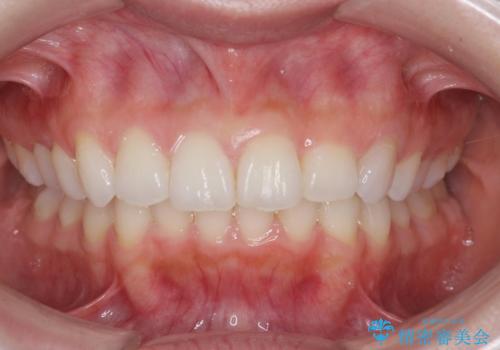

ガタつきがなくなり満足して頂けました。

矯正後は補綴装置をつけないと後戻りしてしまう可能性があるので

補綴装置をしっかりと装着する必要があります。